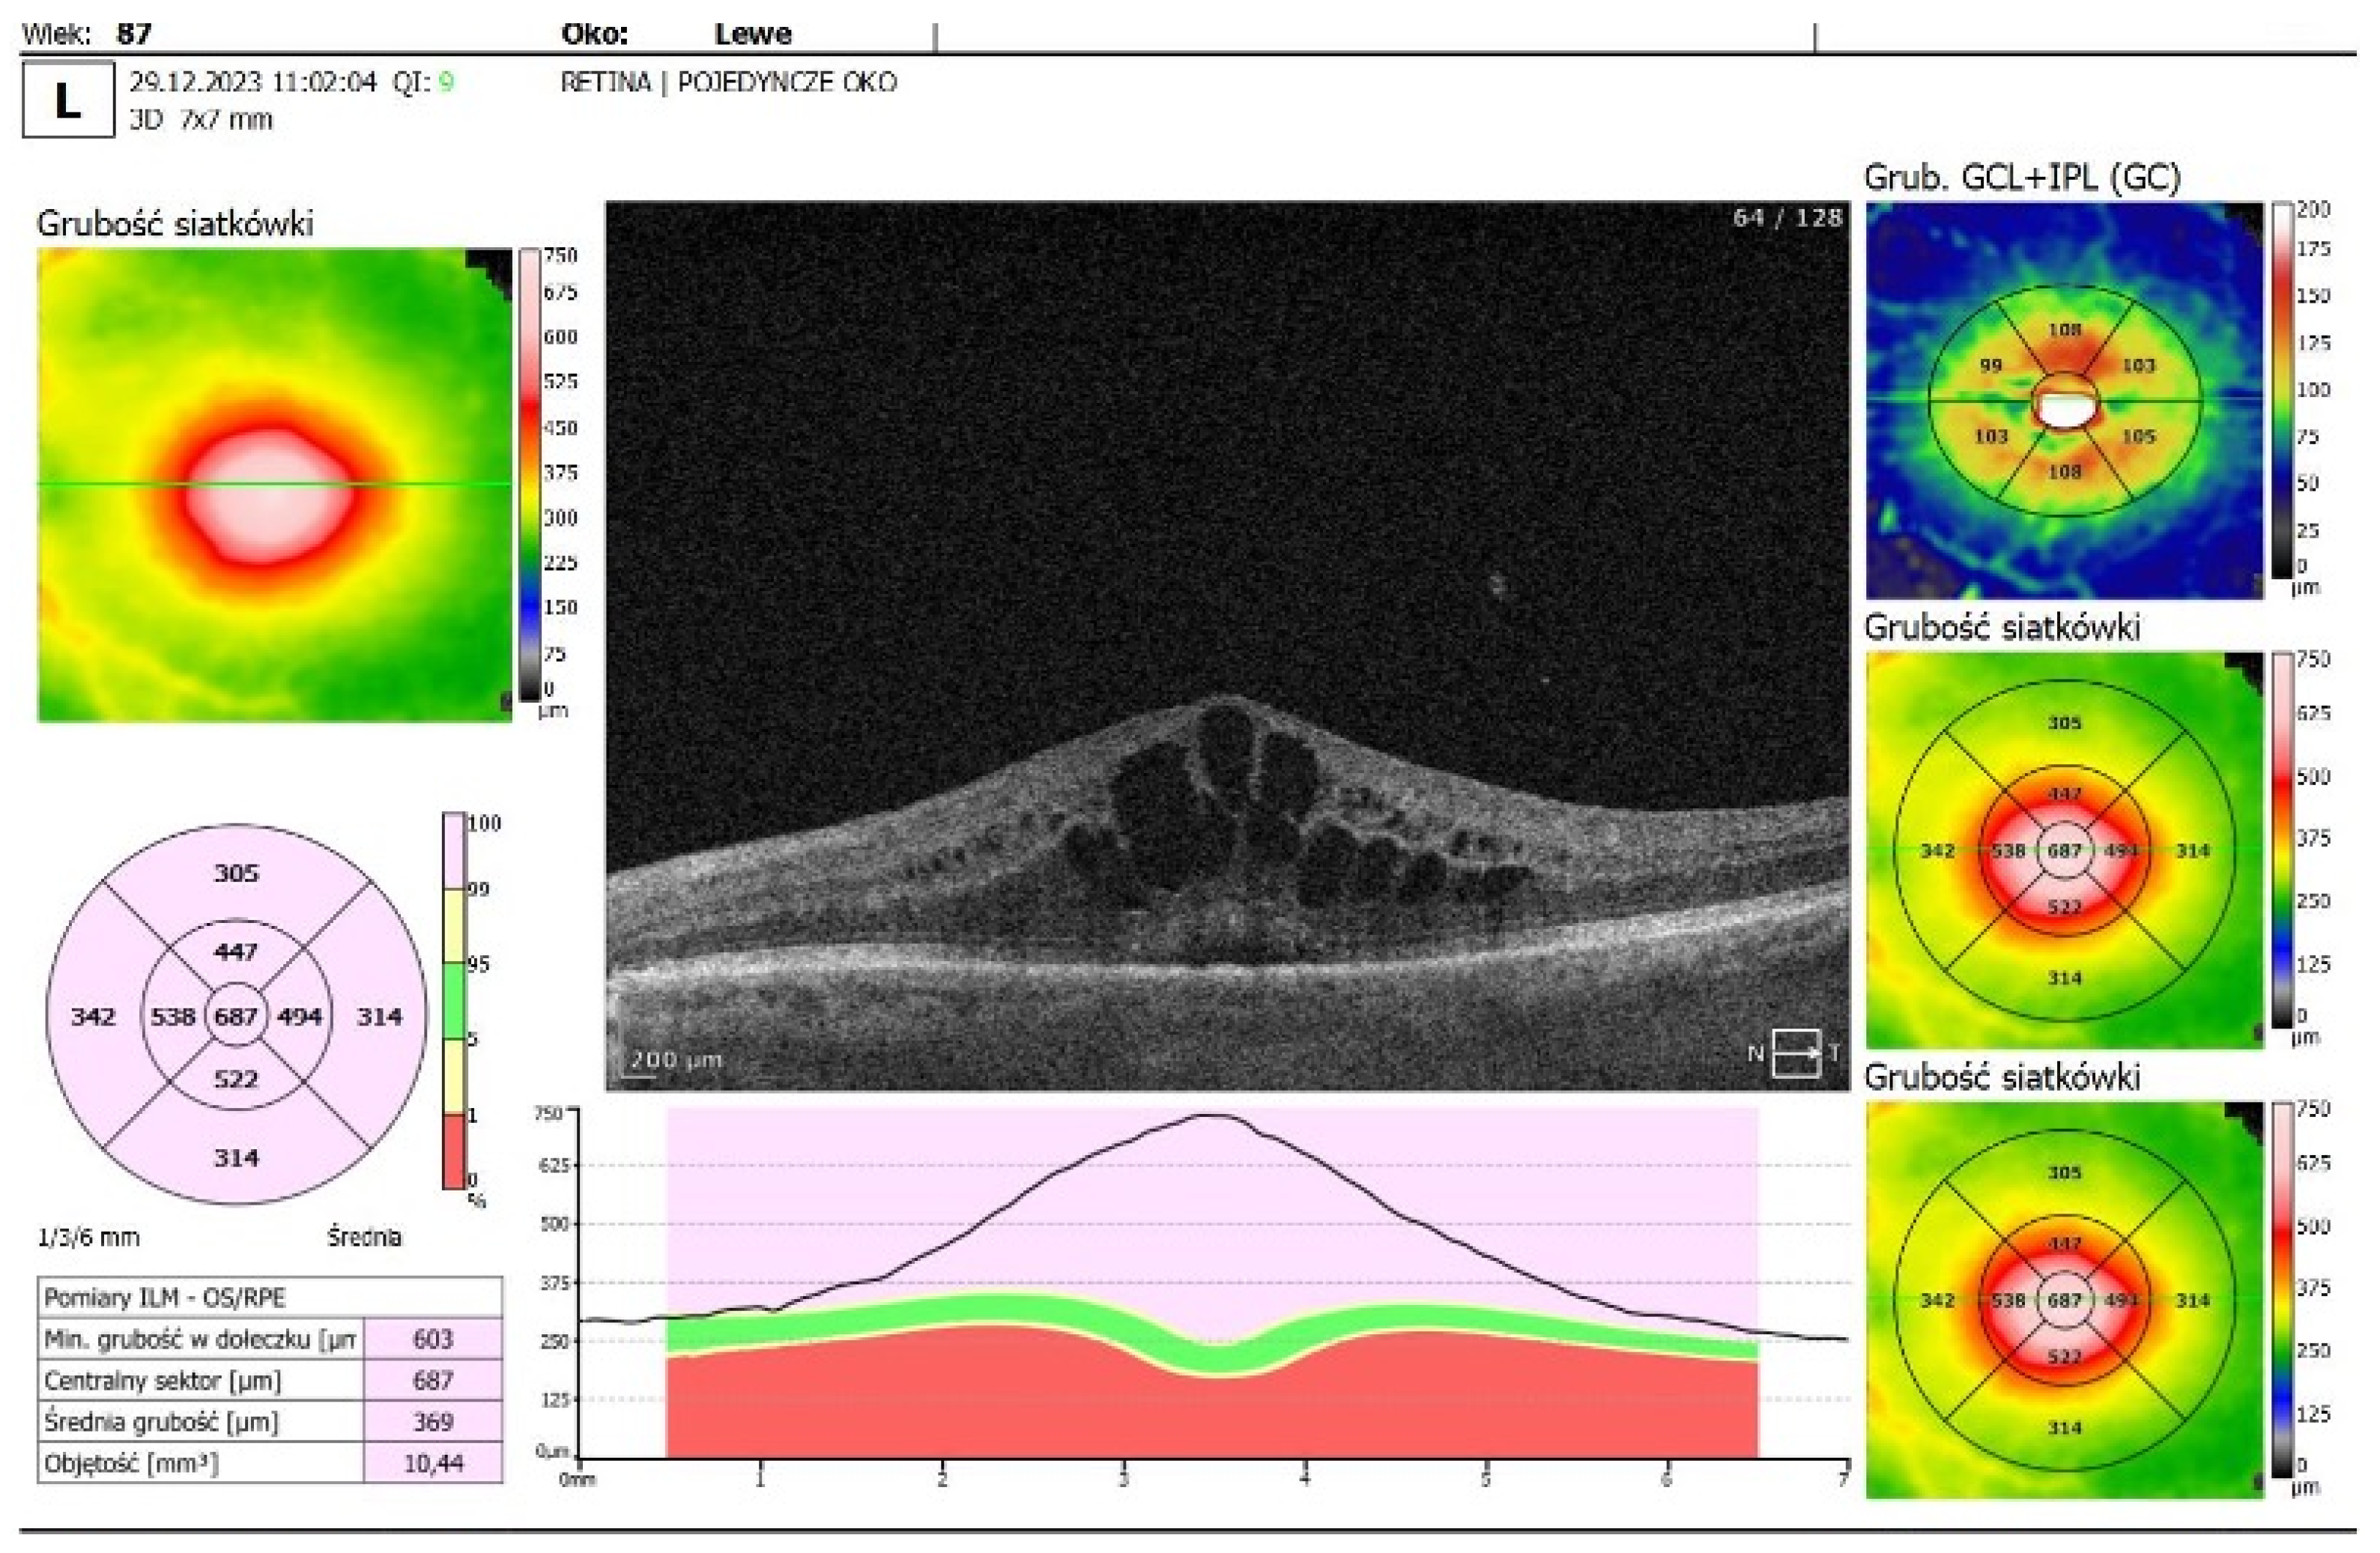

- OCT imaging: Complete resolution of macular edema in the left eye; bilateral choroidal folds and subretinal fluid (SRF) were present (Figure 2C).

| OCT Figure 2C |

No cystoid macular edema in the left eye; residual SRF and choroidal folds in both eyes Fluid next to the optic disc and macular choroidal folds in both eyes |

| OCT | residual submacular subretinal fluid persisted in left eye, fluid next to optic disc resolved and choroidal folds disappeared |